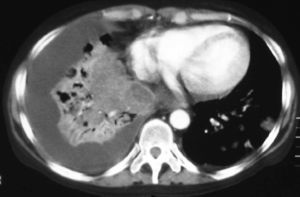

Fig. 4. Tomografía computarizada con contraste intravenoso a la altura de las bases pulmonares.

Mujer de 34 años de edad, con antecedentes de lupus eritematoso de complicado control que obliga a un tratamiento prolongado con dosis altas de corticoides. Presenta clínica de un mes de evolución de astenia, tos y febrícula con sudoración profusa en los últimos 10 días, que evoluciona con deterioro progresivo y disnea de reposo.